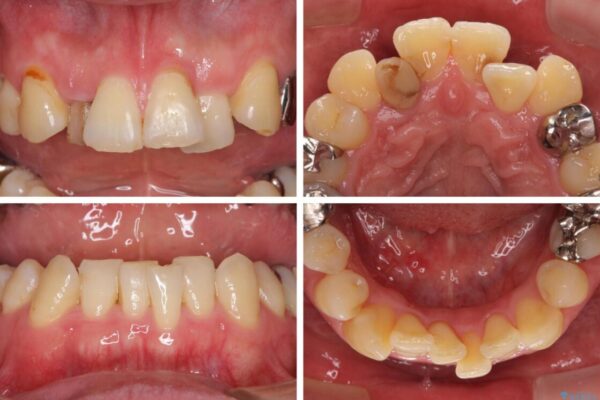

奥歯の痛みと前歯のデコボコを気にして来院された患者様です。

左右下顎の大臼歯は、ともに歯根が破折しており、抜歯が必要な状態でした。

放置したことで炎症による骨吸収が顕著であるため、骨造成を併用してインプラント埋入を行うこととしました。

咬み合わせは受け口傾向であり、上顎前歯の叢生が顕著であったことから、第1小臼歯抜歯による矯正治療も検討しましたが、下顎大臼歯を左右ともに抜歯するため、非抜歯による矯正治療を行うこととしました。

治療前